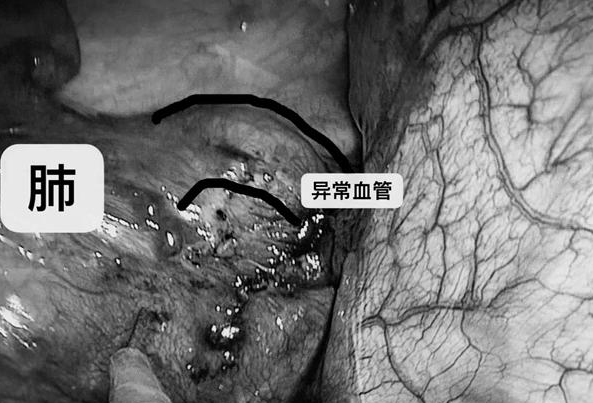

而患兒左側多出來的一葉肺,并不和支氣管相連,其血液供應來自主動脈的一個異常分支,因此無法完成正常的血液循環,“簡單來說,就像是電線短路了一樣。”

隔離肺是胚胎發育缺陷所造成肺的先天性畸形。隔離肺從肺分離出來,不和肺支氣管相通,沒有正常肺的功能。但與主動脈相連接,所以有血供,特別容易受到感染,之所以曉軍之前會咳嗽、出現肺炎,甚至咳血,都是這個隔離肺感染出血